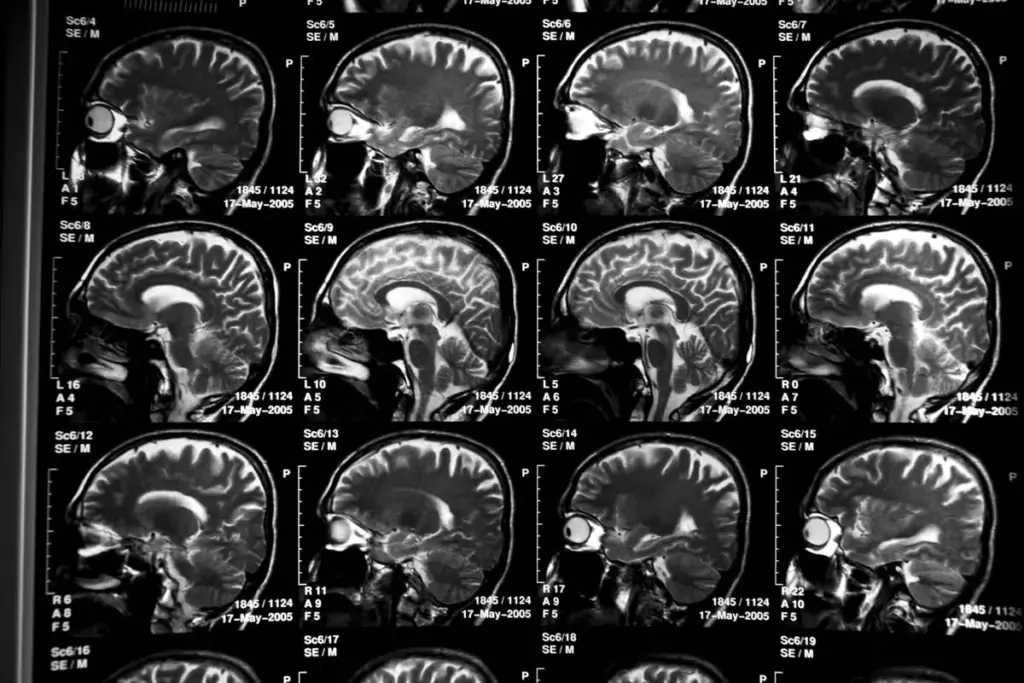

No, screening tests indicate potential cognitive impairment. A formal diagnosis requires comprehensive evaluation, including medical history, lab tests, and imaging.